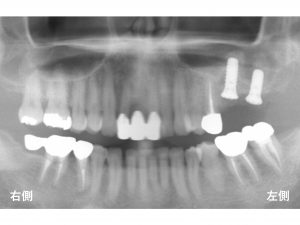

まずは

治療前のレントゲンから見てみましょう!

上顎左側の奥歯が2歯欠損している状態です。

以下がインプラント手術が終わった当日です。

骨とインプラントがしっかりとくっつく(結合)するまで

約3〜4ヶ月待ちます。